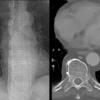

paraspinal lines

Date: 10/23/2010

Views: 3549

Views: 3265

Views: 3132

paraspinal interface